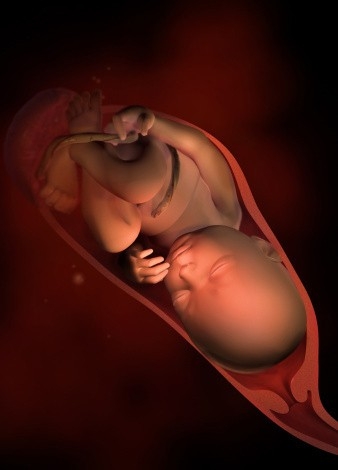

第八个月

胎宝宝身长约40cm,体重约1800g,此时的胎宝宝已经充满整个子宫,生长迅速,活动空间变小,皮下逐渐长出脂肪,大脑迅速发育,眼睛开闭自由,可以辨认和追踪光源。